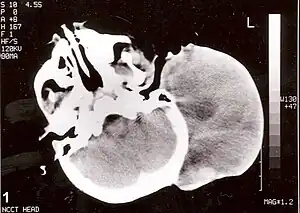

| Non-contrast CT scan of head showing a large mass without any intracranial extension. The diagnosis was post-auricular congenital alveolar rhabdomyosarcoma. | |